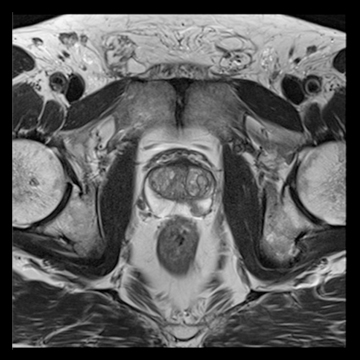

前立腺

高分解能T2

T2

RESOLVE, b=800

and ADC map,